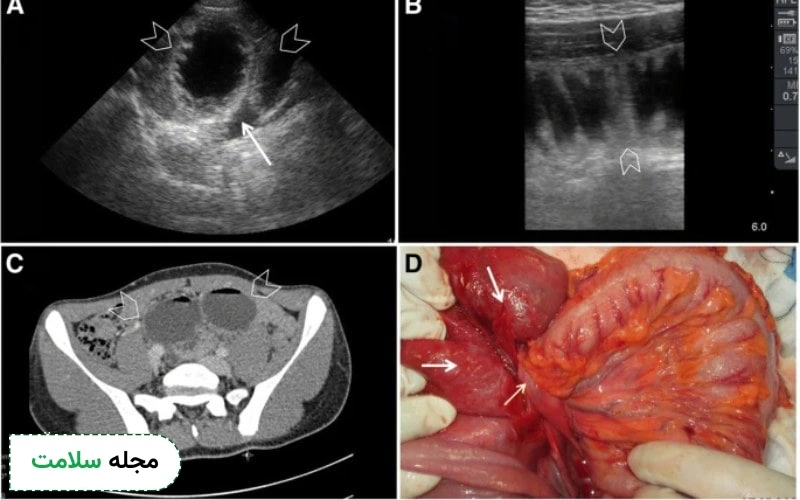

4. سونوگرافی حین عمل

گاهی در طول جراحی برای ارزیابی گسترش سرطان روده به اندام‌های مجاور، به‌ویژه کبد، از سونوگرافی حین عمل استفاده می‌شود. با قرار دادن ترانسدیوسر به‌طور مستقیم روی کبد، جراحان می‌توانند تصاویر لحظه‌ای دریافت کنند که به آن‌ها کمک می‌کند تا احتمالات و روند جراحی را بهتر پیش‌بینی کرده و جلو ببرند. این تکنیک به‌ویژه برای شناسایی متاستازهایی که از طریق سایر روش‌ها قابل مشاهده نیستند مفید است و به برنامه‌ریزی جراحی دقیق‌تر می‌انجامد.

5. سونوگرافی برای متاستازهای خارج روده

یکی از کاربردهای دیگر سونوگرافی برای ارزیابی متاستازهای احتمالی از سرطان روده به اندام‌های دیگر مانند کبد و غدد لنفاوی است. این روش غیرتهاجمی و با توانایی ارائه نتایج فوری، به پزشکان کمک می‌کند تا تومورهای ثانویه را شناسایی کرده و از آن‌ها برای هدایت تست‌های تشخیصی بیشتر استفاده کنند.

اما نتایج غیرنرمال ممکن است نشانه‌ای از مشکلات جدی‌تر در روده باشد. یکی از مهم‌ترین یافته‌های غیرنرمال در سونوگرافی، توده‌ها یا ضخامت غیرطبیعی دیواره روده است. ضخیم شدن دیواره روده می‌تواند نشان‌دهنده التهاب، عفونت یا حتی سرطان باشد.

تومورهای سرطانی معمولاً باعث تغییرات ساختاری در دیواره روده می‌شوند که به وضوح در تصاویر سونوگرافی قابل مشاهده هستند. در این حالت، پزشک ممکن است از بیمار بخواهد که آزمایش‌های بیشتری مانند کولونوسکوپی یا بیوپسی برای تایید تشخیص انجام دهد.

علاوه بر این، سونوگرافی قادر است غدد لنفاوی بزرگ‌شده را نیز شناسایی کند. غدد لنفاوی بزرگ شده می‌توانند نشانه‌ای از انتشار سرطان به این اندام‌ها باشند، زیرا سیستم لنفاوی به‌طور معمول اولین مقصد برای متاستازهای سرطان است. شناسایی این غدد لنفاوی می‌تواند پزشکان را آگاه کند تا در کاهش گسترش سرطان به دیگر نواحی بدن درمان مناسبی را تجویز کنند.

یکی دیگر از نتایج غیرنرمال در سونوگرافی، ضایعات کبدی است که می‌تواند به متاستازهای کبدی اشاره داشته باشد. سرطان روده به‌ویژه در مراحل پیشرفته، به‌طور شایع به کبد متاستاز می‌کند و سونوگرافی می‌تواند تصاویر دقیقی از وضعیت کبد ارائه دهد. در صورتی که ضایعات کبدی در سونوگرافی مشاهده شود، این نیاز به آزمایش‌های بیشتر مانند سی‌تی‌اسکن یا ام‌آرآی برای ارزیابی دقیق‌تر گسترش سرطان به کبد دارد.